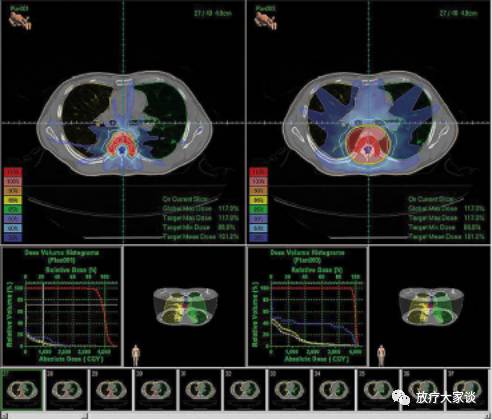

4.12计划评价

4,12,1  DVH

放疗计划系统有哪些放射治疗计划系统(TPS)介绍_https://www.jmylbn.com_新闻资讯_第12张

4.12.2  计划对比

放疗计划系统有哪些放射治疗计划系统(TPS)介绍_https://www.jmylbn.com_新闻资讯_第13张